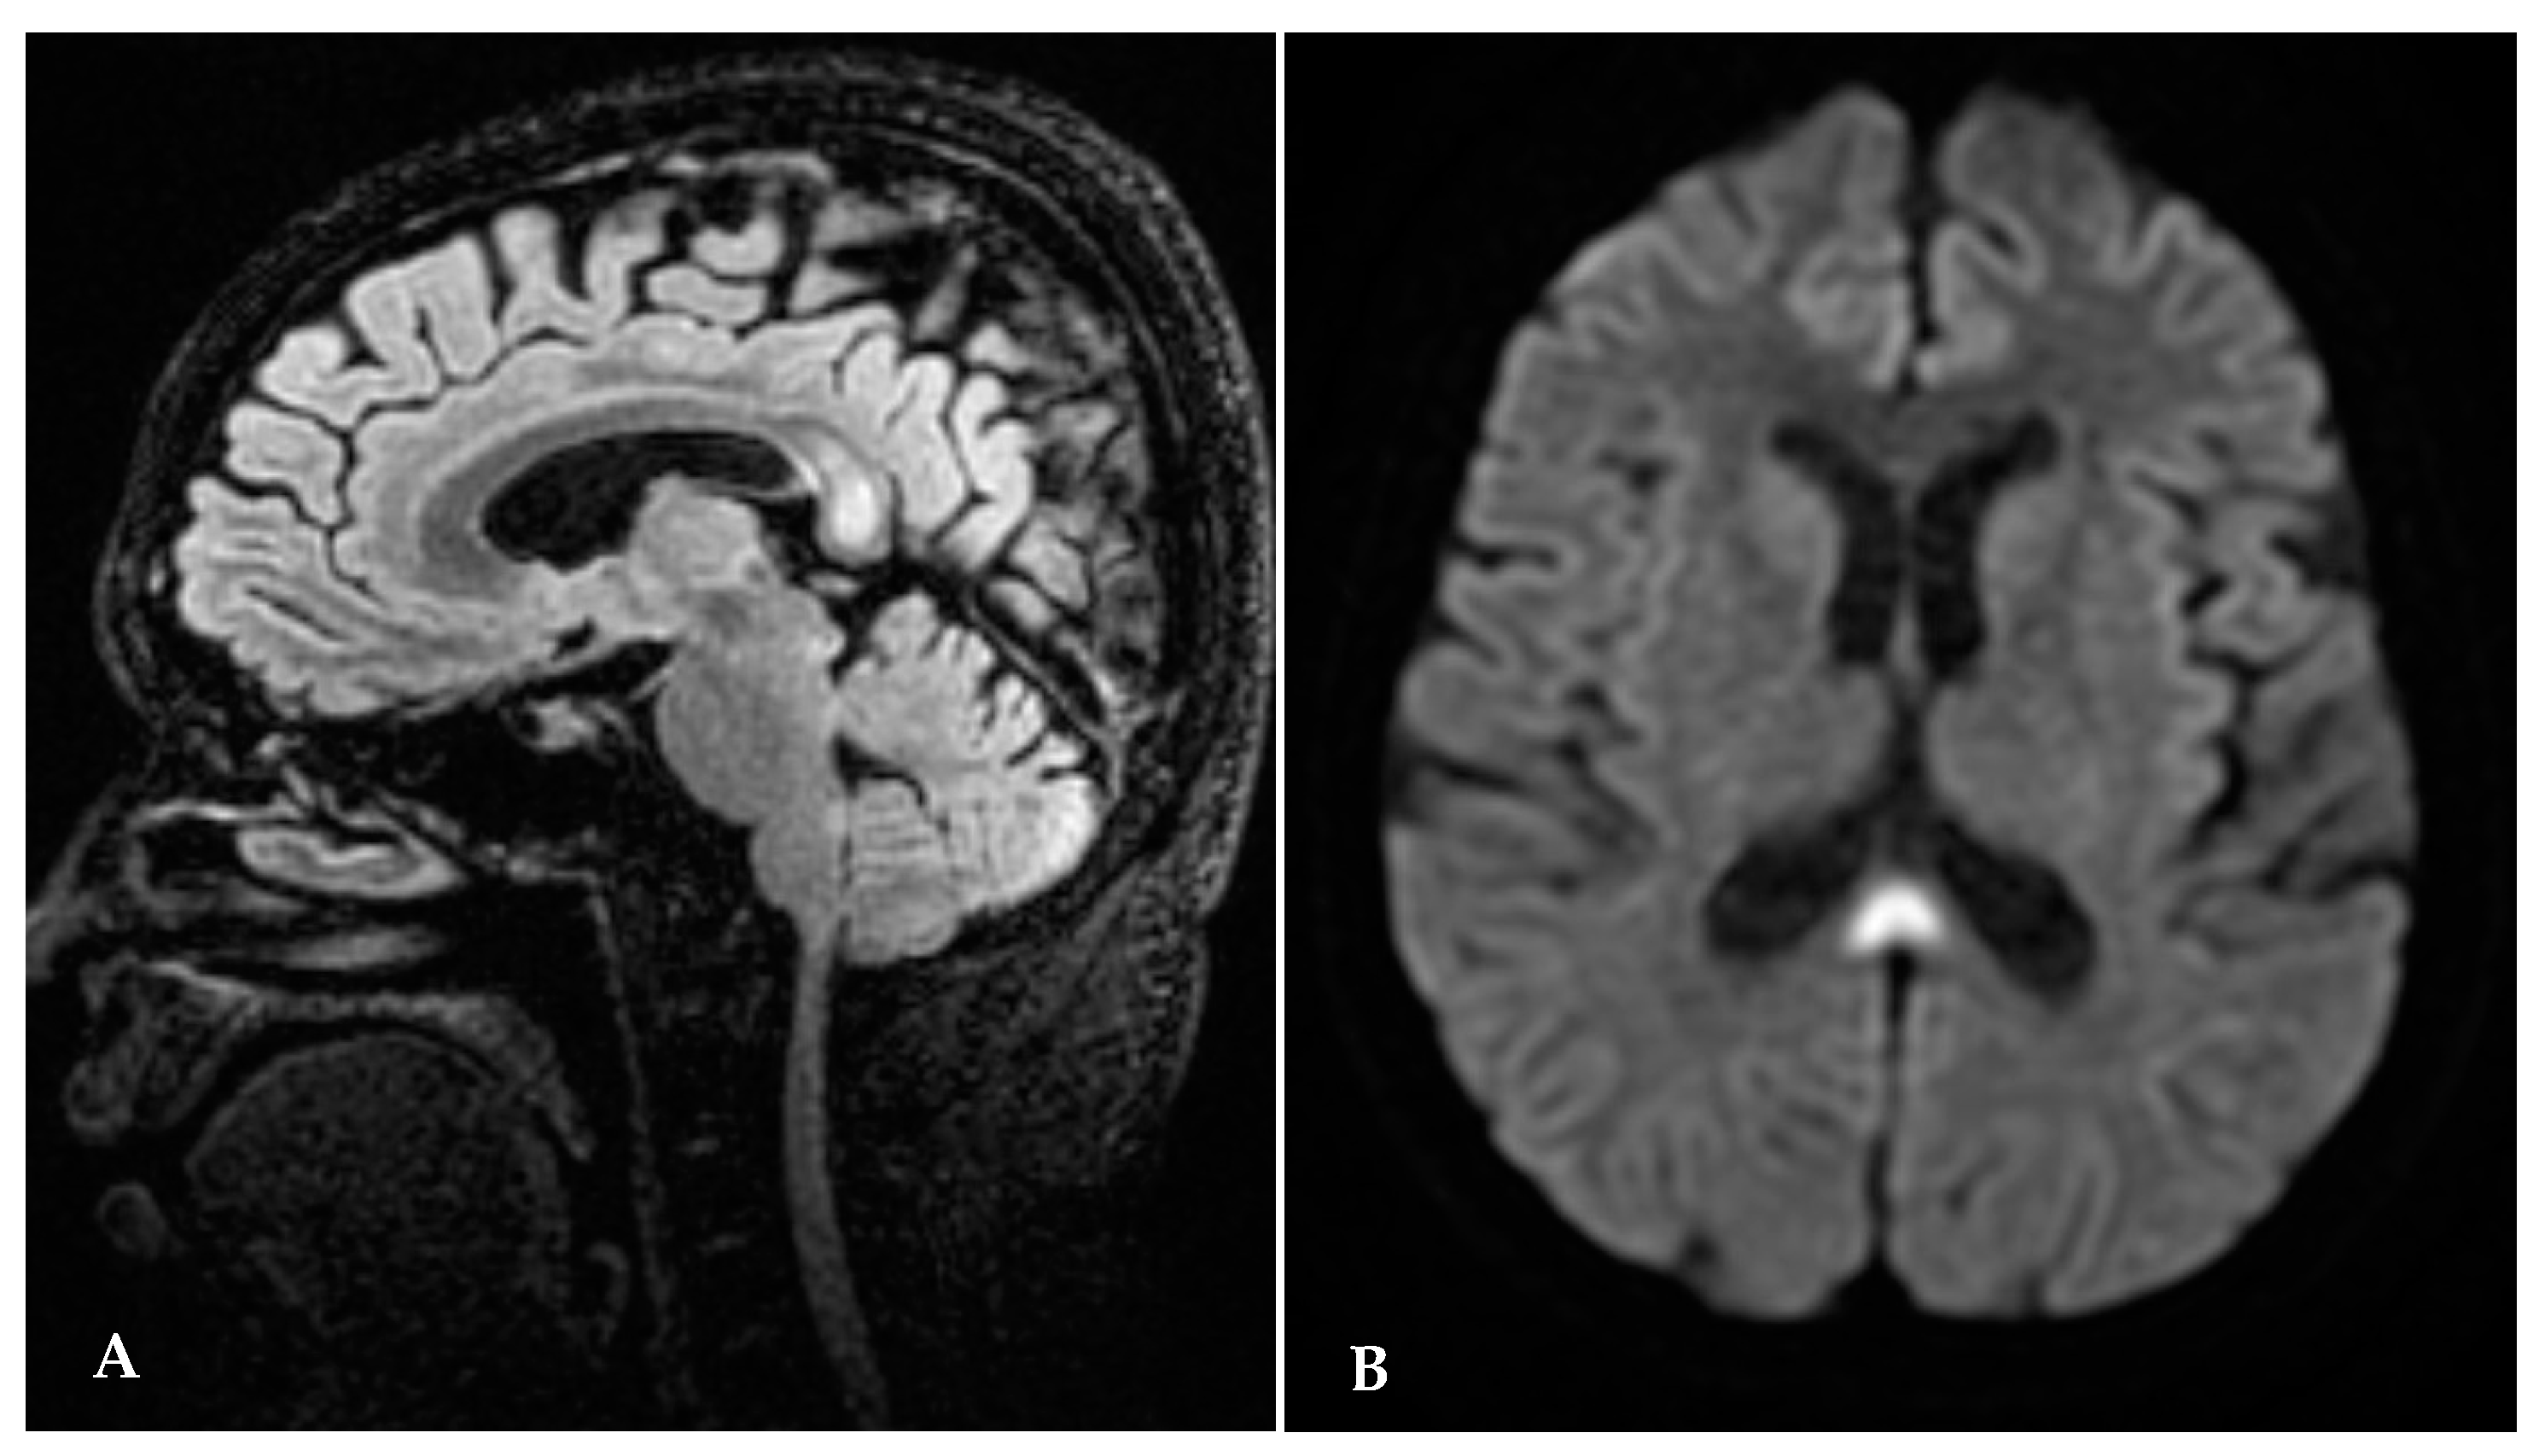

Following admission, the patient was referred first to a diabetologist, who diagnosed “overt diabetes”. This is not a coincidence since thiamine demand increases in metabolism of carbohydrates. Immediately after the diabetologic consultation, patient started insulin therapy and glucose monitoring, after which she underwent a full eye examination, which showed vertical downbeat nystagmus, papilledema, an oval retinal hemorrhage on inferotemporal vascular arcade; all such signs point to a pattern of central nervous system involvement. After the ophthalmological examination, the patient underwent a brain MRI, which showed an abnormal signal in the splenium of corpus callosum and a symmetrical hyperintensity in thalamic and periaqueductal areas (Figure 1A,B), all findings indicative of WE. The patient then underwent a neurological examination, which showed ataxia with impaired walking and nystagmus in all directions of gaze.

Figure 1.

(A,B) Brain MRI after admission: abnormal signal in the splenium of corpus callosum.

Brain MRI performed after the admission showed an abnormal signal in the splenium of corpus callosum and a symmetrical hyperintensity in thalamic and periaqueductal areas (Figure 1).